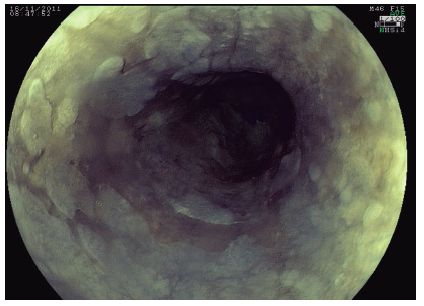

Placas elevadas de esófago: no todo es acantosis glucogénica

Paciente de 57 años de edad, sexo femenino, que consultó por dispepsia tipo dolor epigástrico, sin síntomas ni signos de alarma (disfagia, adelgazamiento, hematemesis, anemia o repercusión general). Se realizó videogastroscopía (VGC) que mostró a nivel esofágico, de manera difusa y en toda su extensión, múltiples placas blanquecinas, de 3 a 10 mm de diámetro, algunas de ellas confluentes (Figura 1). Se realizó una cromoendoscopía electrónica con FICE (Fujinon Intelligent Chromoendoscopy) con el objetivo de conseguir una mejor caracterización de las lesiones y de sus límites (Figura 2). Se tomaron múltiples biopsias que fueron enviadas para el estudio anatomopatológico.